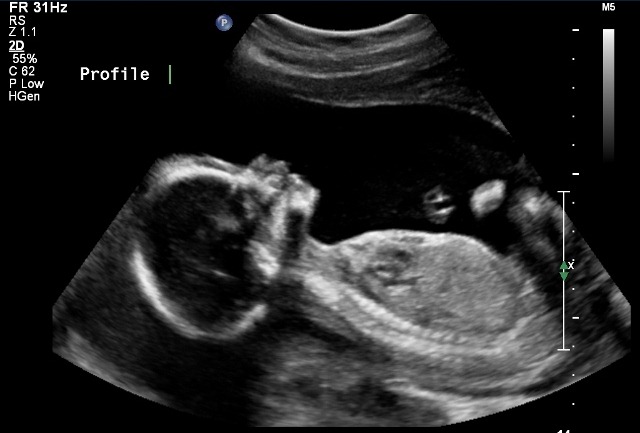

Hulumtuesit australianë zbuluan se marrja e vitaminës B3 gjatë shtatzanisë mund të zvogëlojë rrezikun e problemeve të lindjes dhe të abortit.

Në një hulumtim 12 vjeçar të realizuar në Institutin e Hulumtimeve “Victor Chang Cardiac” në Sidnej, zbulohet se marrja e vitaminës B3 gjatë shtatzanisë e cila njihet si “niasin”, mund ta ul rrezikun e problemeve gjatë lindjes dhe të abortit.